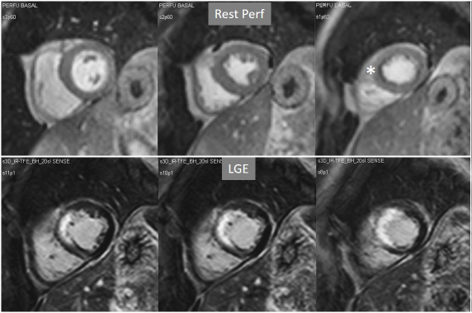

The presence of inducible residual peri-infarction ischemia in a territory with a previous MI has been addressed by the consideration of the extension of a stress perfusion defect in comparison with that of the LGE. Those defects with equal size on both sequences would be labelled as “fixed” (Fig. 16), while those perfusion defects exceeding the area of MI would be considered as “partially reversible” (Fig. 17), independently of rest perfusion studies. The diagnostic performance of the latter finding for the diagnosis of a residual significant stenosis in the infarct-related artery has been found to be adequate, though a good deal of cases with apparently fixed defects had also significantly obstructed arteries [46].

Fig. 16.Stress/Rest perfusion in chronic myocardial infarction. Perfusion defect during stress (performed in first place) (black arrow), not present at rest, matching the area of LGE (white arrow) in a case of large anterior subendocardial MI.

Fig. 17.Stress/Rest perfusion in chronic myocardial infarction. Perfusion defect during stress (performed in first place) (white arrow), not present at rest, fairly larger than the region of LGE (black arrow) in a patient with a subendocardial inferior MI.